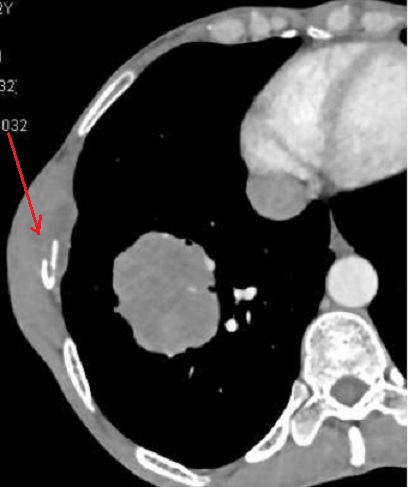

Espect metastatique de

tumefaction de la paroi thoracique droit et de

lyse de destruction osseuse correspondence du

côté droit d'une tumeur metastatique ( fleche rouge

) à origine de cancer pulmonaire ++ droit . Image

radiologique TDM en coupe axial |